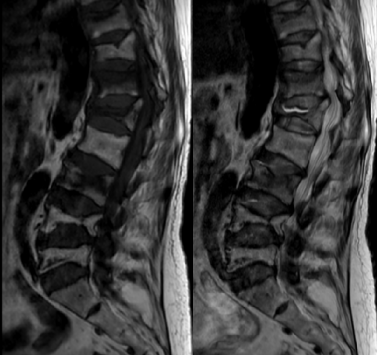

了解到徐州市中医院骨伤科不仅手法复位技术有绝招,微创手术也做得相当出色,她慕名前来,找到了张镇主任。张镇在详细了解谢某的病情后,为她制定了个性化治疗方案。首先保持卧床休息,以减少腰部和髋部的进一步损伤,并给予止痛药物以缓解疼痛;随后,进行了系列常规检查,以便全面掌握身体状况,同时,紧急进行了胸腰椎核磁共振检查,以确定椎体压缩的数量和程度。

检查结果显示,谢某的身体状况良好,但骨折情况却相当严重。除了右侧股骨颈骨折伴有错位外,还有胸10、胸12、腰1、腰3和腰5等5个椎体的新鲜骨折。面对如此严重的多发骨折,传统的手术方式显然不是最佳选择,因为就算是年轻人也难以承受长时间的手术和麻醉。针对这一特殊情况,张镇提出了分多次进行微创手术的方案。这样既可以减少手术对患者身体的负担,又能达到最佳手术治疗效果。